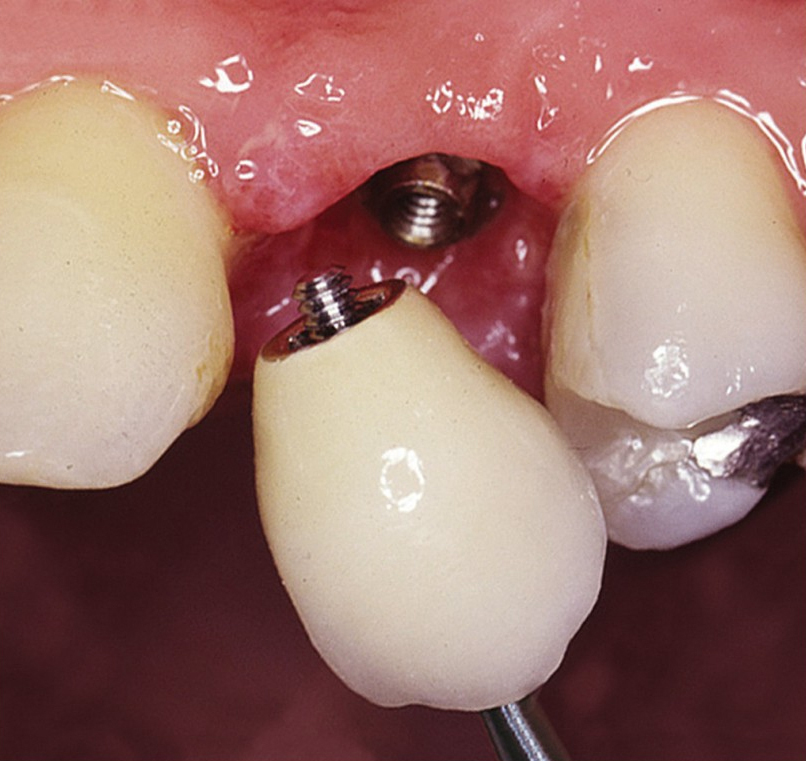

Klasickým příkladem a indikací pro použití implantátu je ztráta jednoho zubu (v tomto případě v předním – frontálním úseku) v jinak zdravém, nepoškozeném chrupu.

Nejčastější příčinou takové ztráty je sportovní nebo dopravní úraz.

Náhrada jednoho zubu pomocí implantátu je možná také v postranním úseku chrupu. Při ztrátě většího počtu zubů ve frontálním nebo postranním úseku může být mezer uzavřena větším počtem jednotlivých implantátů.

Při ošetření pomocí jednotlivých implantátů zůstávají sousední zuby neporušené – intaktní. Při klasickém ošetření pomocí můstků musejí být tyto zuby obroušeny!